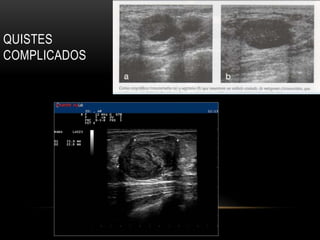

MICROQUISTES

AGRUPADOS

QUISTES

COMPLICADOS